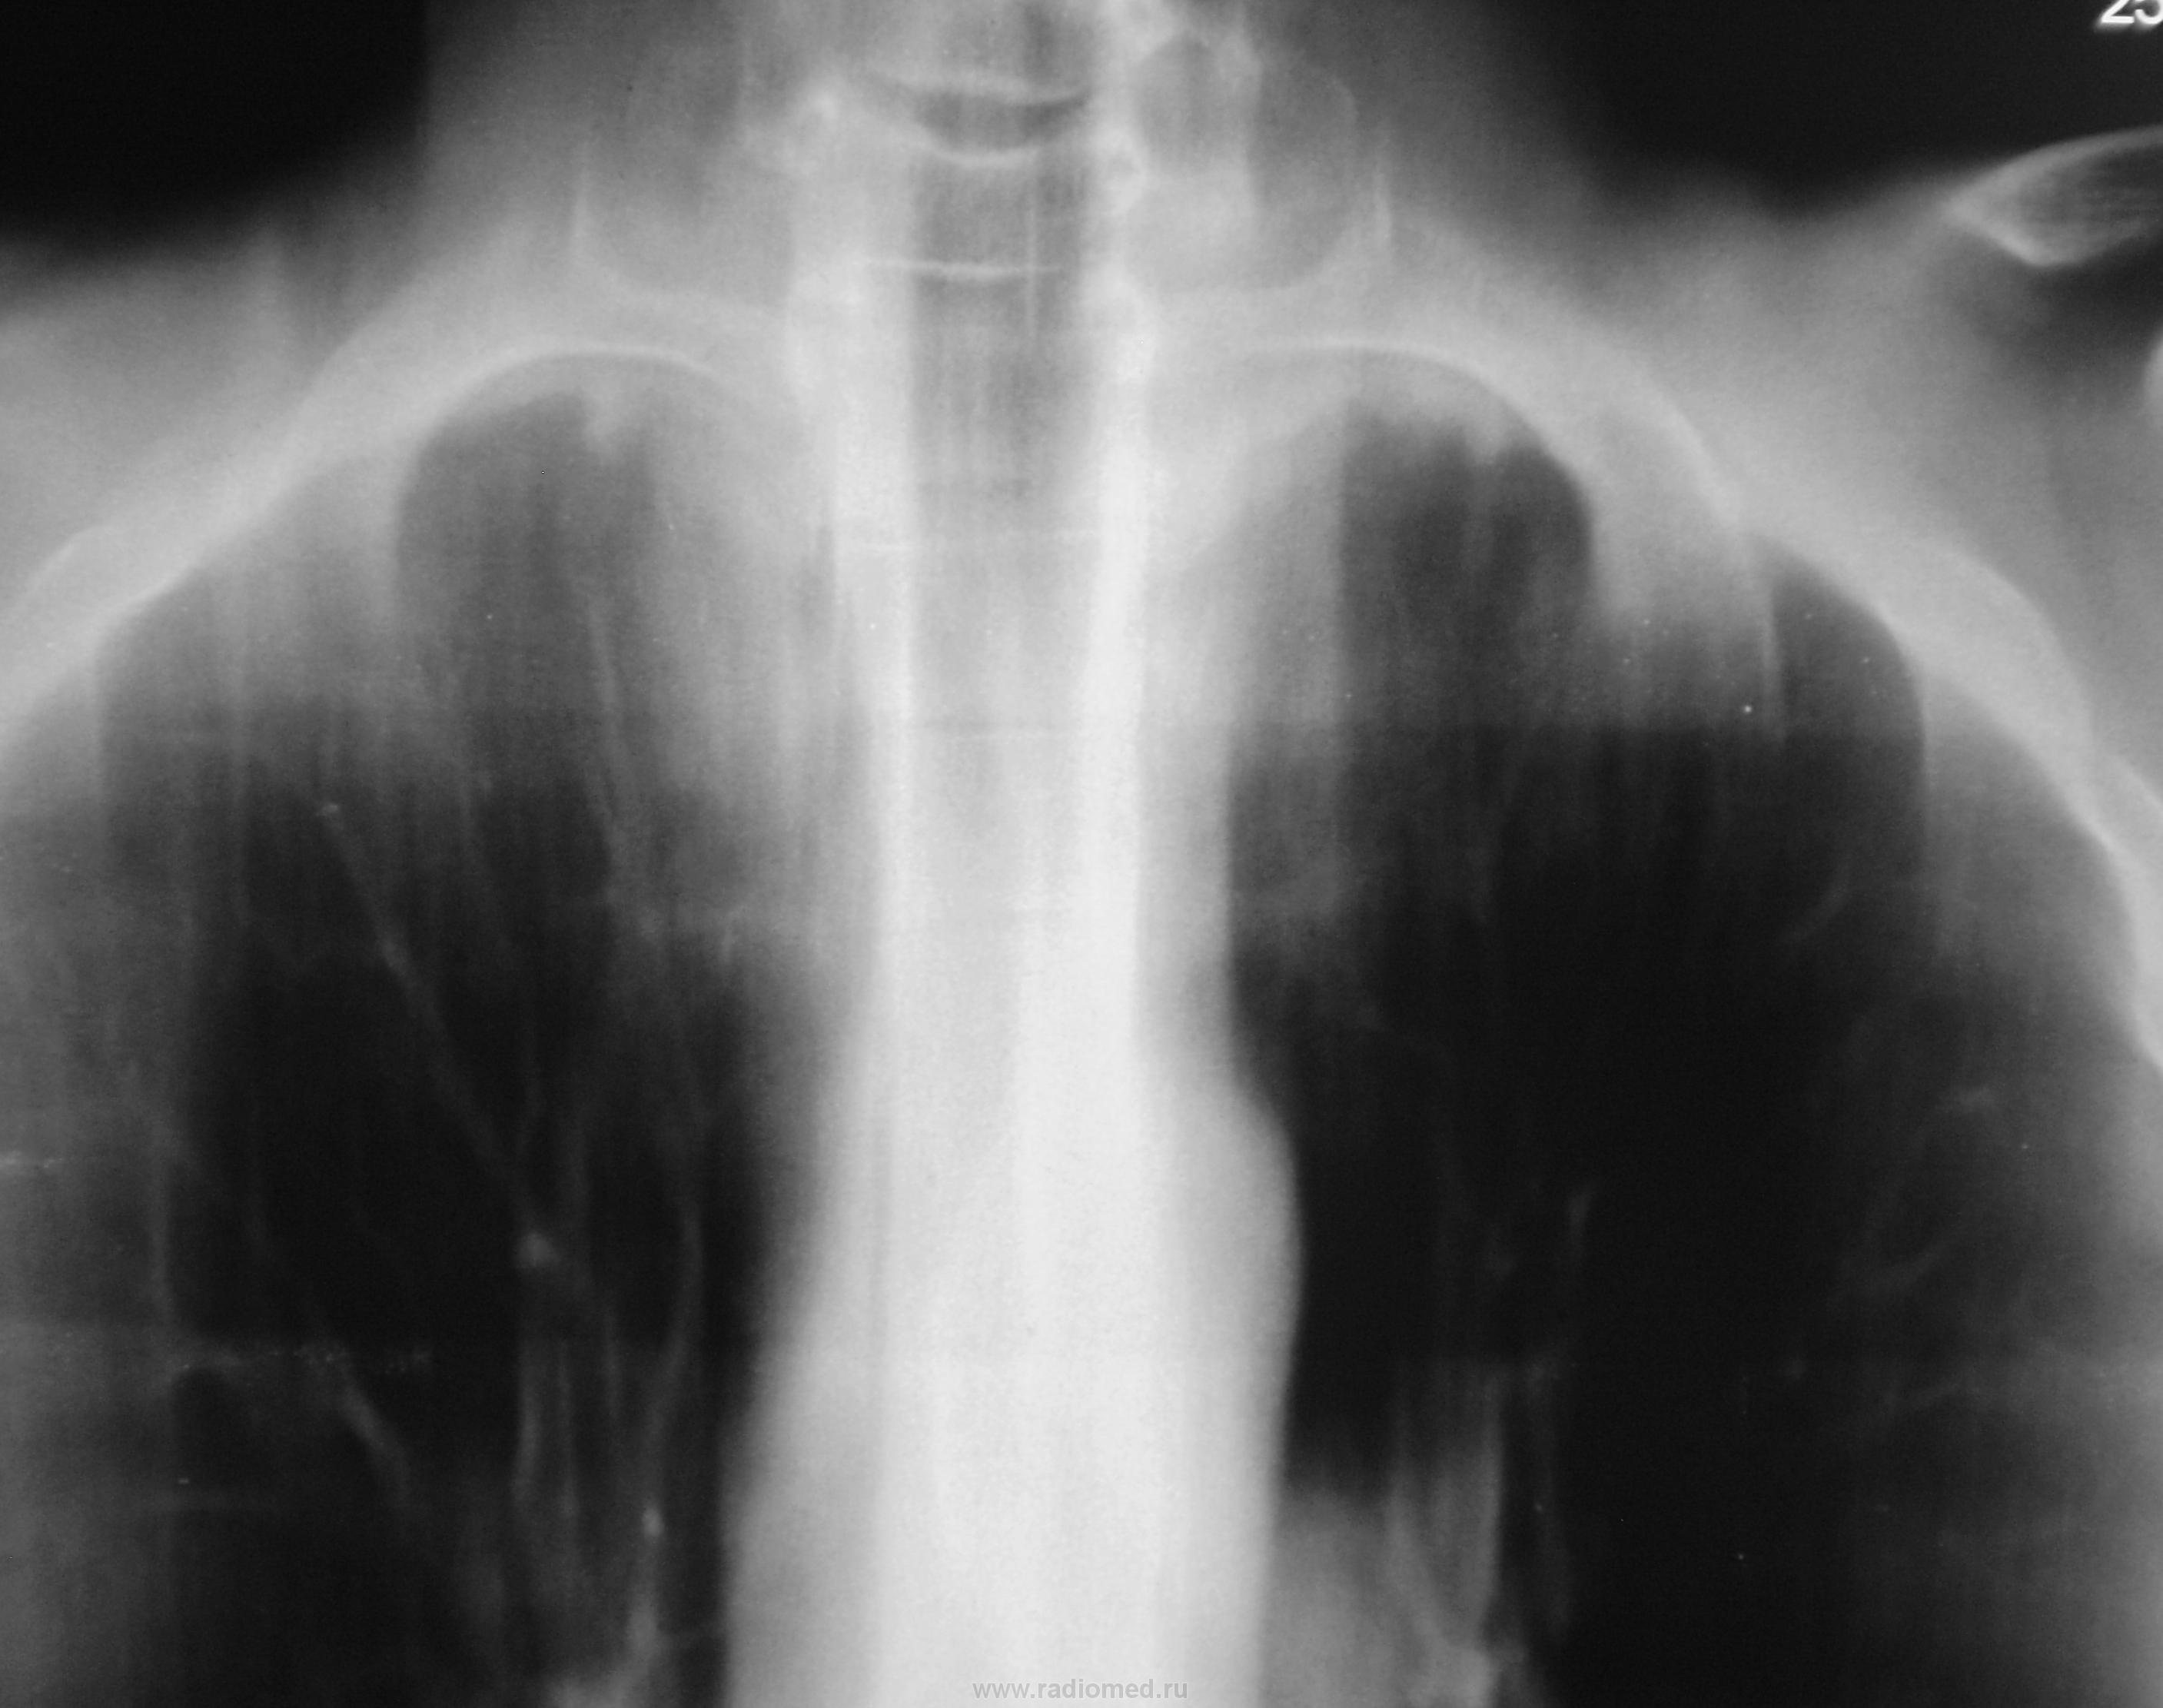

Пол пациента: Мужской пол Тип патологии: Воспалительное заболевание неинфекционной природы Область исследования: Грудная клетка и верхние дыхательные пути Методы исследования: Rg Один срез. Какие мнения будут по поводу верхушек? https://radiomed.ru/sites/default/files/styles/case_slider_image/public/user/12/2.p8220012a.jpg?itok=DBx6V3Ip https://radiomed.ru/sites/default/files/styles/case_slider_image/public/user/12/3.p8220013.jpg?itok=DXkjmgLZ https://radiomed.ru/sites/default/files/styles/case_slider_image/public/user/12/4.p8220013a.jpg?itok=wC_CAi7E ID:14919 Пнд, 22/08/2011 - 17:38 #1 Игорь Иванович Не на сайте Был на сайте: 3 года 10 месяцев назад Зарегистрирован: 23.01.2010 - 14:56 Публикации: 3695 Я б не придрался, но вначале было слово, ой - обзорная... Втр, 23/08/2011 - 08:12 #2 vevo Не на сайте Был на сайте: 11 лет 2 месяцев назад Зарегистрирован: 15.08.2011 - 00:32 Публикации: 77 Ошибаться как правило свойственно всем, здесь норм Втр, 23/08/2011 - 15:36 #3 Катенёв Валенти... Не на сайте Был на сайте: 7 лет 1 месяц назад Зарегистрирован: 22.03.2008 - 22:15 Публикации: 54876 vevo wrote: Ошибаться как правило свойственно всем, здесь норм Так можно "норму" писать? Втр, 23/08/2011 - 17:19 #4 skos72 Не на сайте Был на сайте: 14 лет 4 месяцев назад Зарегистрирован: 29.06.2011 - 17:36 Публикации: 37 Я бы обозначил видимые изменения как плевро-апикальные наложения, а в остальном норма Втр, 23/08/2011 - 20:33 #5 Kat Не на сайте Был на сайте: 12 лет 7 месяцев назад Зарегистрирован: 19.04.2011 - 19:10 Публикации: 365 слева похоже на плевро-апикальные наложения (контур на протяжении нескольких см волнистый), а вот справа контур плевры ровный и на его фоне плотный очаг. Временно отсутствую на сайте... Втр, 23/08/2011 - 21:53 #6 фтизиорентгенолог Не на сайте Был на сайте: 4 года 11 месяцев назад Зарегистрирован: 03.06.2011 - 18:43 Публикации: 16 я тоже думаю,что очаги на фоне плевро-апикльных наслоений исключить нельзя,для уточнения наличия очаговых изменений необходима КТ ОГК Втр, 23/08/2011 - 22:02 #7 Катенёв Валенти... Не на сайте Был на сайте: 7 лет 1 месяц назад Зарегистрирован: 22.03.2008 - 22:15 Публикации: 54876 фтизиорентгенолог wrote: я тоже думаю,что очаги на фоне плевро-апикльных наслоений исключить нельзя,для уточнения наличия очаговых изменений необходима КТ ОГК А, если КТ в районе нет? Ср, 24/08/2011 - 01:01 #8 фтизиорентгенолог Не на сайте Был на сайте: 4 года 11 месяцев назад Зарегистрирован: 03.06.2011 - 18:43 Публикации: 16 ну тогда... прицельные ТМГ на верхушки через 0,5см., сравнить с архивом и ставить: -очаговый Твс активность? -посттуберкулезные изменения -группа R-o+ Ср, 24/08/2011 - 07:31 #9 Игорь Иванович Не на сайте Был на сайте: 3 года 10 месяцев назад Зарегистрирован: 23.01.2010 - 14:56 Публикации: 3695 Дайте ж обзорную... Ср, 24/08/2011 - 14:17 #10 Катенёв Валенти... Не на сайте Был на сайте: 7 лет 1 месяц назад Зарегистрирован: 22.03.2008 - 22:15 Публикации: 54876 Нету обзорной. Делали контроль после флюшки без меня, я был в отпуске. Чт, 25/08/2011 - 02:14 #11 svet Не на сайте Был на сайте: 1 год 11 месяцев назад Зарегистрирован: 07.05.2010 - 19:10 Публикации: 201 по этому срезу можно сказать что нечего сказать или в срез просто не попали не очагов не плевроапикальных реакций.

слева похоже на плевро-апикальные наложения (контур на протяжении нескольких см волнистый), а вот справа контур плевры ровный и на его фоне плотный очаг.

я тоже думаю,что очаги на фоне плевро-апикльных наслоений исключить нельзя,для уточнения наличия очаговых изменений необходима КТ ОГК

прицельные ТМГ на верхушки через 0,5см., сравнить с архивом и ставить:

-очаговый Твс активность?

-посттуберкулезные изменения

-группа R-o+

Нету обзорной. Делали контроль после флюшки без меня, я был в отпуске.